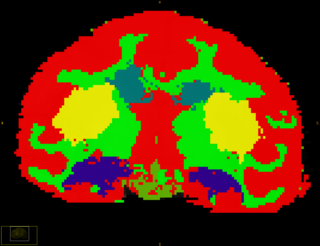

Subcortical Segmentation of Rhesus subject